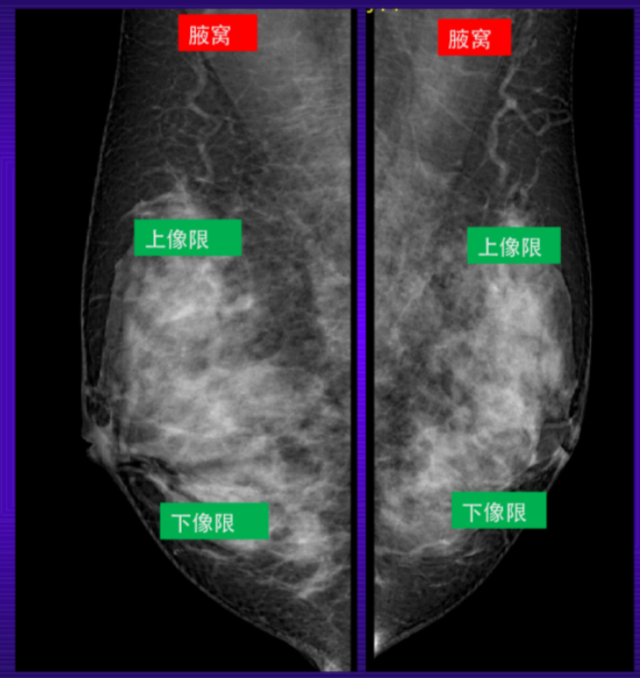

乳腺钼靶

乳腺钼靶检查,相对更适合40岁以上的女性。

乳腺的彩超和乳腺的钼靶,是目前临床中最常见、最简便的两种检查方法。这两种方法不存在哪一种比另一种更好的说法,它们在临床中作用是互补的,比如对于年轻患者的乳房结节,以及诊断重点在腋窝或锁骨上、下的淋巴结,彩超比钼靶的效果更好,但对于年龄较大,尤其是绝经后的患者,通常钼靶要好于超声。另外,钼靶可以发现一些超声不能发现的钙化,而对于有乳头溢液的患者,钼靶可以通过造影发现乳管内的病变。

钼 靶

乳腺脂肪小叶